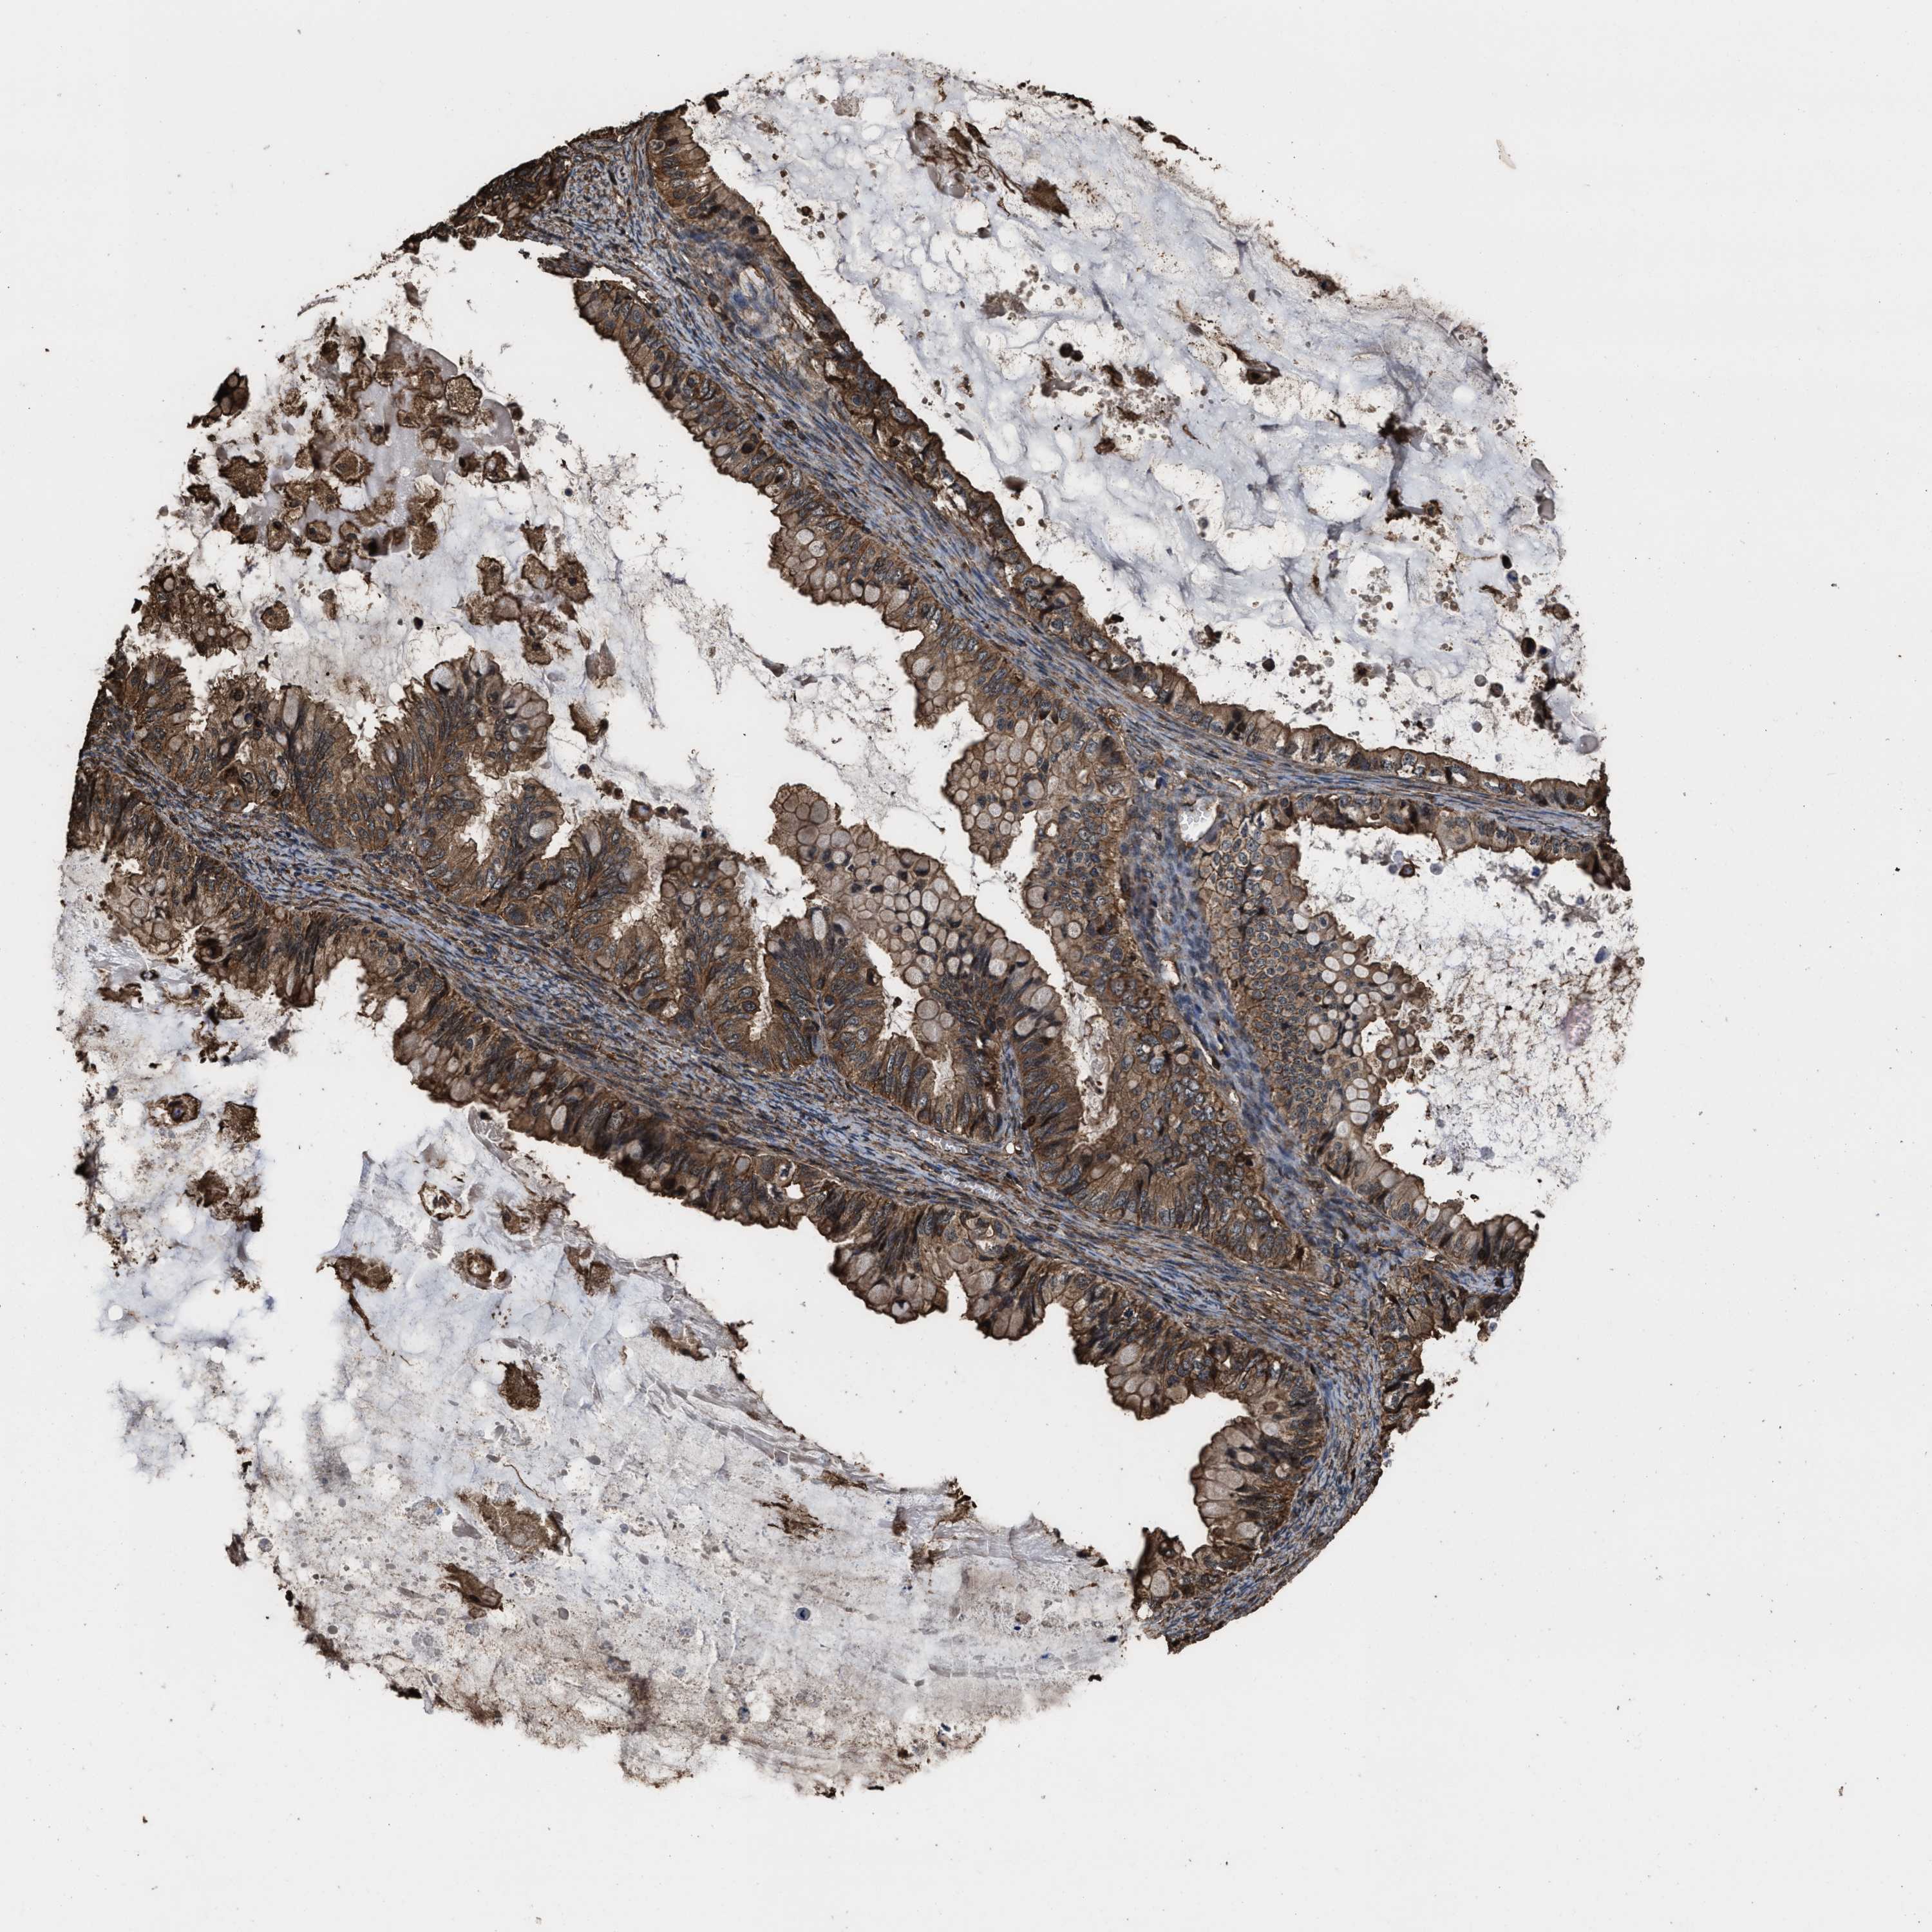

OVARIAN CANCER - Protein expressioni

A mouse-over function shows sample information and annotation data. Click on an image to view it in a full screen mode. Samples can be filtered based on level of antibody staining by selecting one or several of the following categories: high, medium, low and not detected. The assay and annotation is described here.

Note that samples used for immunohistochemistry by the Human Protein Atlas do not correspond to samples in the TCGA dataset.

Antibody stainingi

Antibody staining in the annotated cell types in the current human tissue is reported as not detected, low, medium, or high, based on conventional immunohistochemistry profiling in selected tissues. This score is based on the combination of the staining intensity and fraction of stained cells.

Each image is clickable and will lead to virtual microscopy that enables deeper exploration of all samples and also displays staining intensity scores, fraction scores and subcellular localization as well as patient and tissue information for each sample.

Antibody HPA021133

Staining

High

Medium

Low

Not detected

Intensity

Strong

Moderate

Weak

Negative

Quantity

>75%

75%-25%

<25%

None

Location

Nuclear

Cytoplasmic/membranous

Cytoplasmic/membranous,nuclear

Cystadenocarcinoma, serous, NOS

Carcinoma, endometroid

Cystadenocarcinoma, mucinous, NOS

Carcinoma, NOS